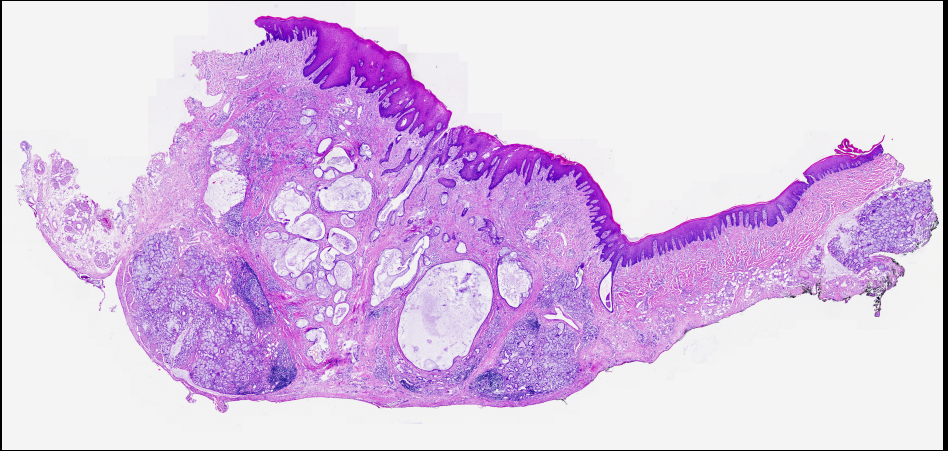

Serrated adenom Traditional Serrated Adenom